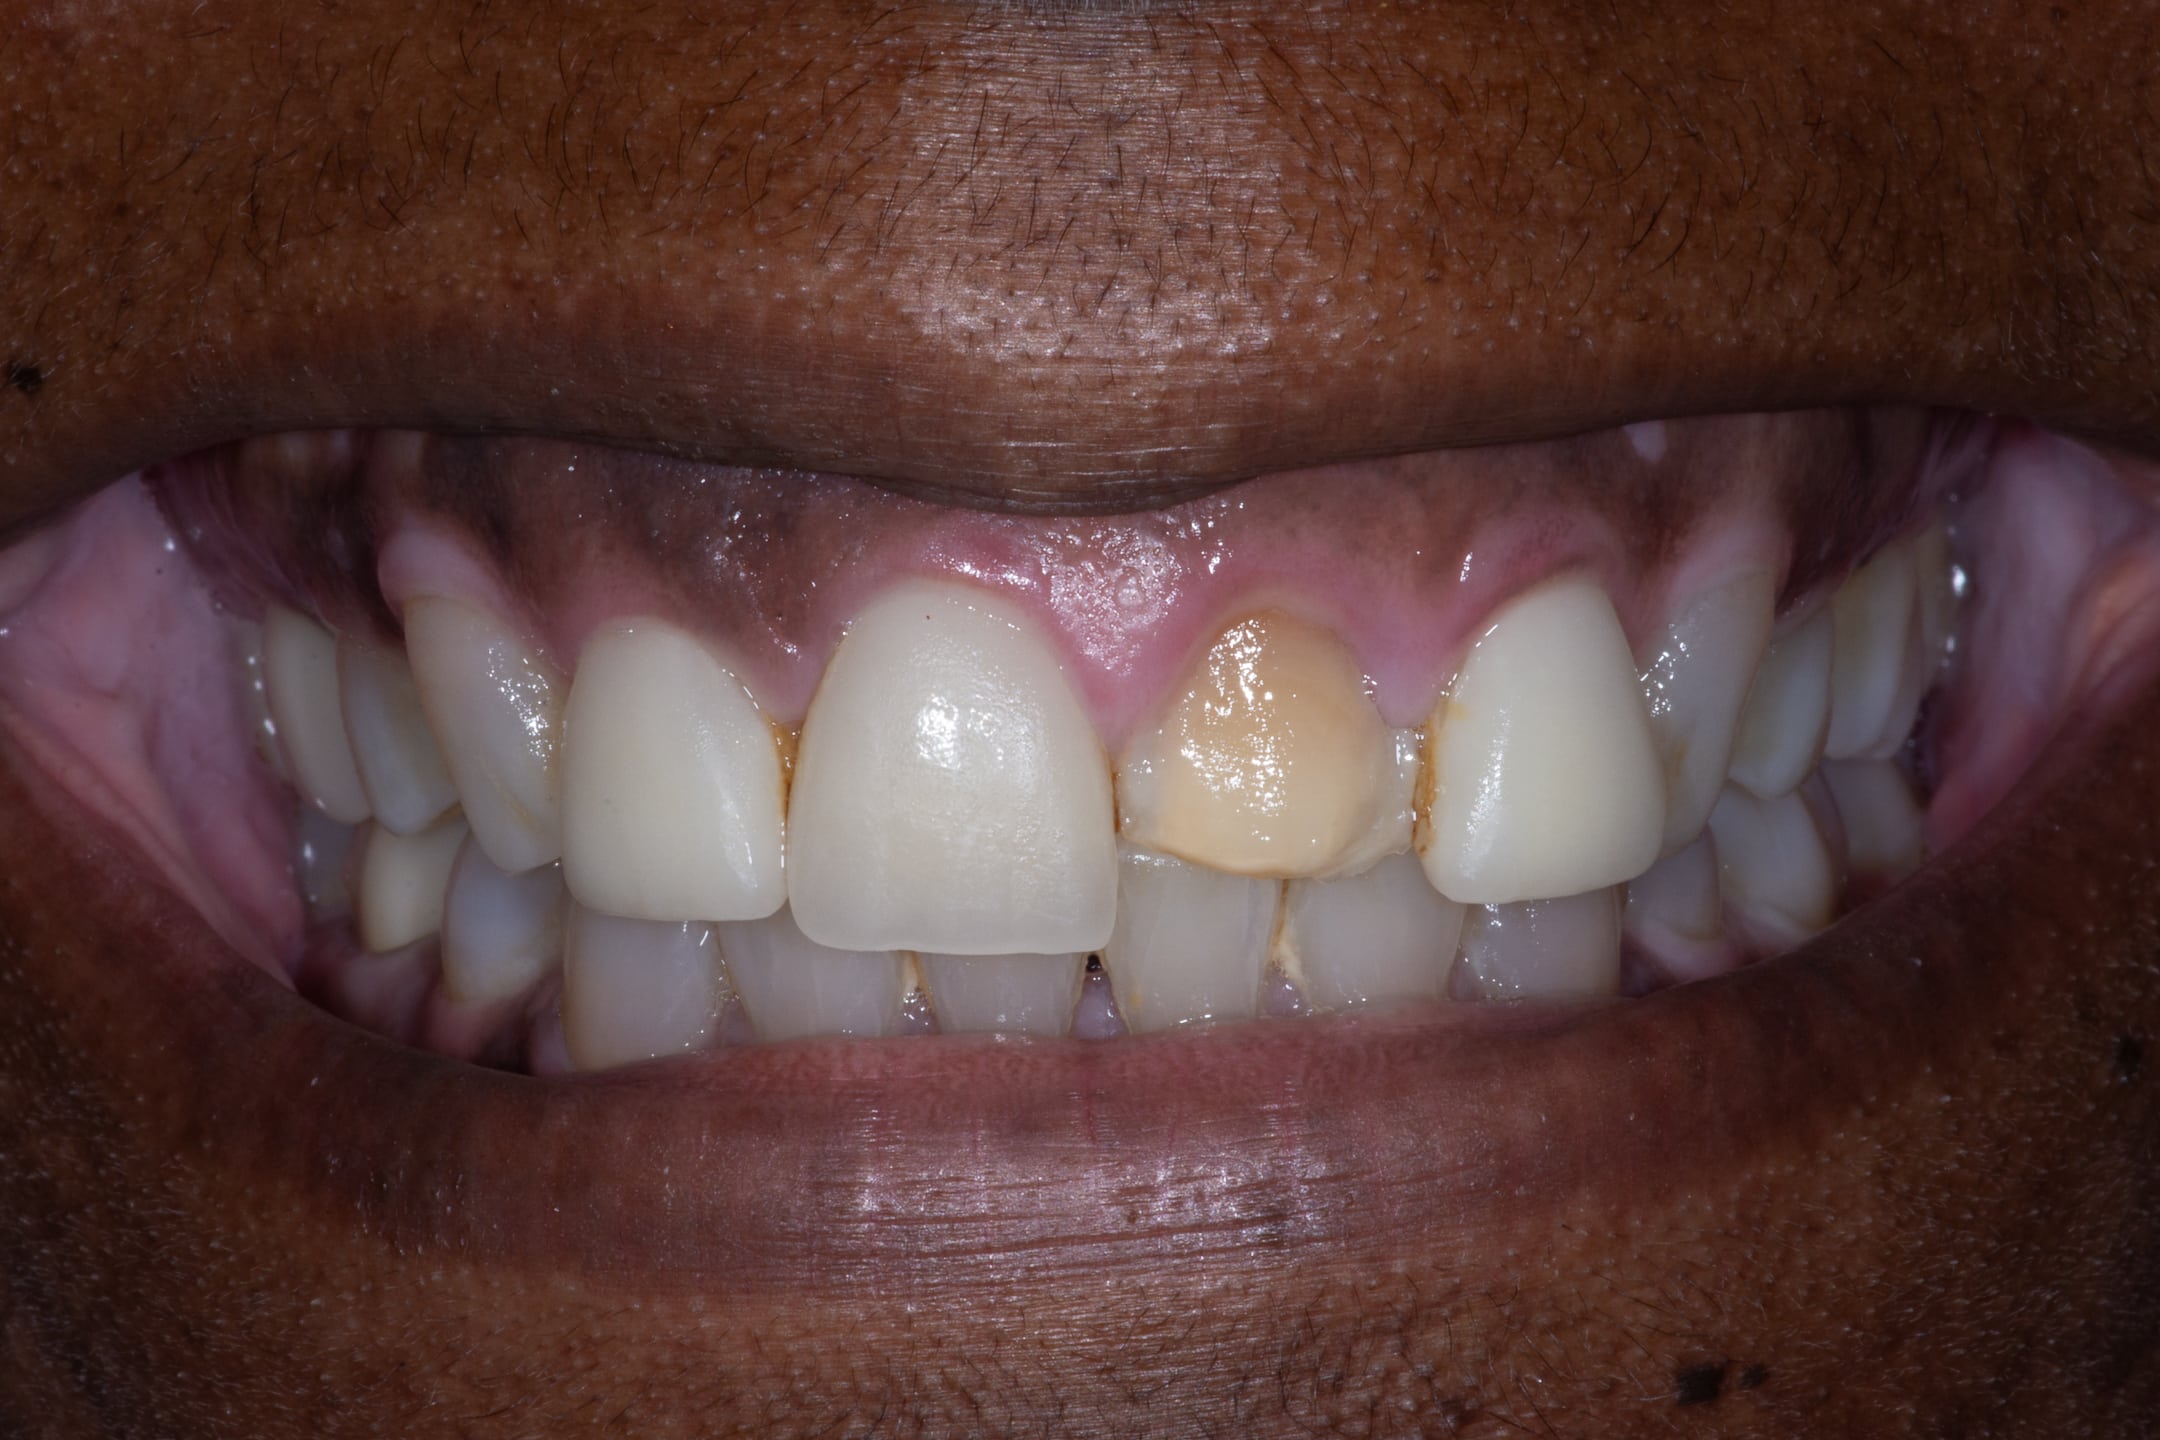

This patient presented to us with veneers that were only two years old, which continued to “pop off.”

The teeth had been aggressively prepared for the four veneers.